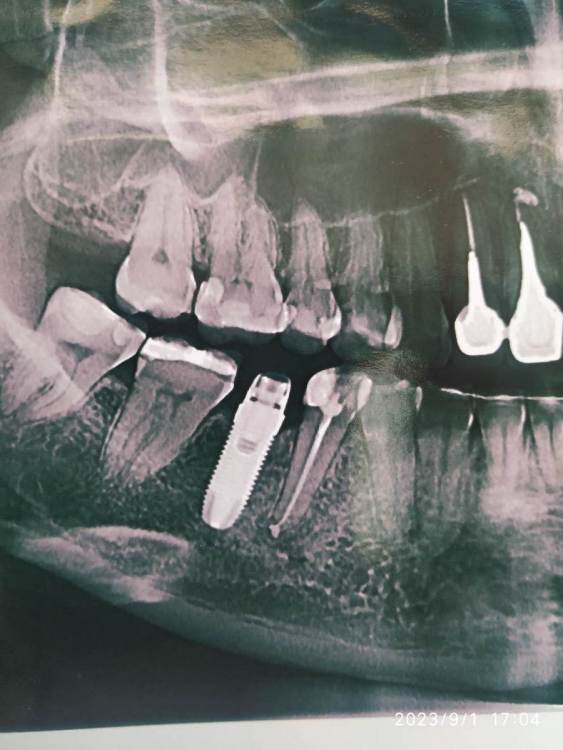

gum Опубликовано 1 сентября, 2023 Поделиться Опубликовано 1 сентября, 2023 Здравствуйте. Подскажите пожалуйста что за имплантат? Ссылка на комментарий

Nazim_NV86 Опубликовано 19 октября, 2023 Поделиться Опубликовано 19 октября, 2023 Нобель кажется Ссылка на комментарий